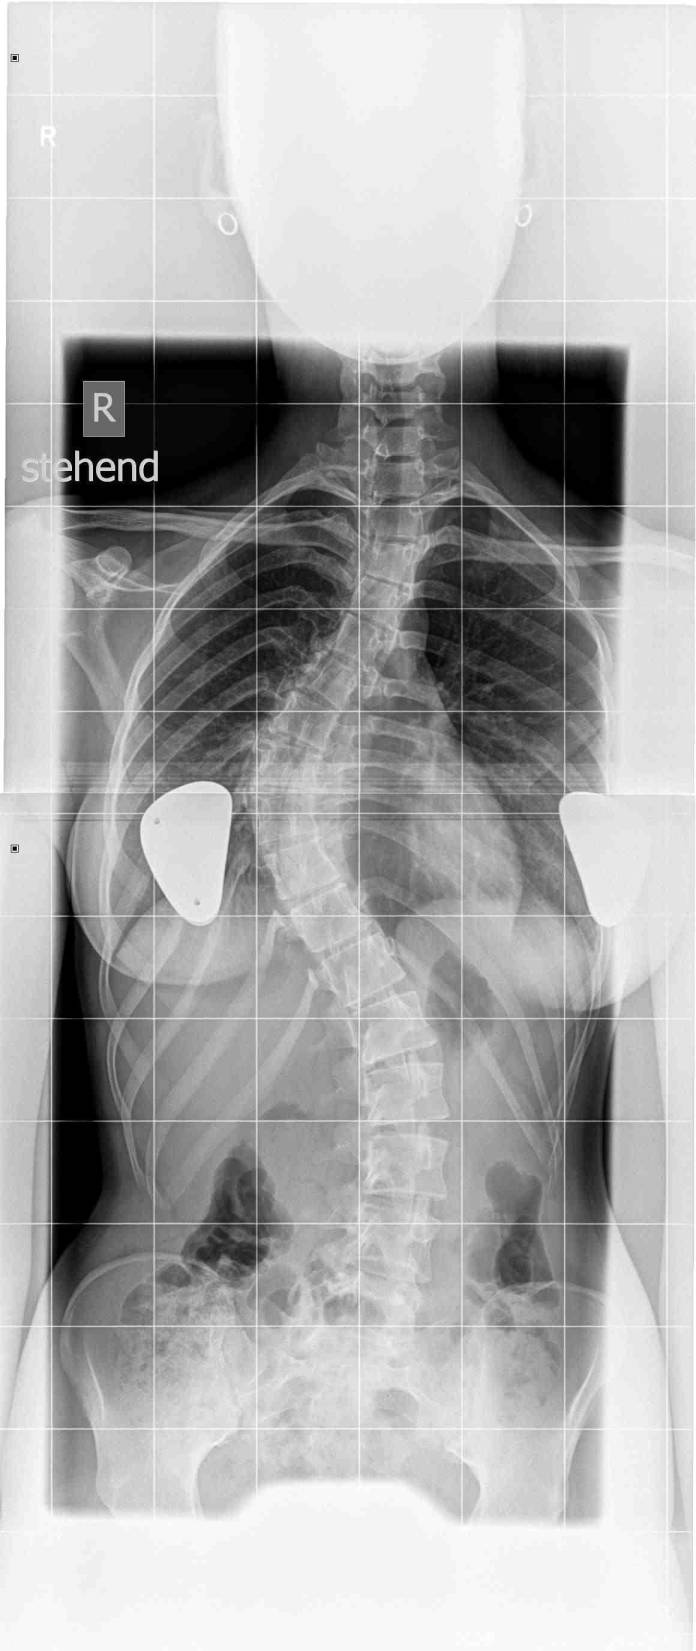

Prof. Halm: Das klassische Merkmal einer Skoliose ist die Rumpfasymmetrie. Bei der Aufsicht von hinten auf den Rücken erkennt man die Seitverbiegung der Wirbelsäule mit gleichzeitiger Fehlrotation der Gliederkette, so dass sich bei Vorliegen der Skoliose in der Brustwirbelsäule ein typischer Rippenbuckel entwickelt, bei Vorliegen in der Lendenwirbelsäule ein Lendenwulst. Bei einer doppelbogigen Skoliose, also s-förmigen Skoliose liegen beide Merkmale vor. Als Folge kommt es meistens dann auch zum Schulterschiefstand, d.h. eine Schulter steht höher als die andere. Ebenso resultiert eine Taillenasymmetrie, d.h. auf der einen Seite verflacht das Taillendreieck, auf der anderen Seite ist es betont. Das wird häufig als Beckenverschiebung oder Beckenfehlstand fehlinterpretiert.

Prof. Halm: Skoliosen bis ca. 20 Grad und ohne Nachweis einer Zunahme im Verlauf können beobachtet und mit skoliosespezifischer Krankengymnastik behandelt werden. Hier hat sich die Therapie nach Katharina Schroth etabliert (Schroth-Therapie) Skoliosen mit Zunahme des Winkels über 20 Grad (bis ca. 40-45 Grad thorakal und bis ca. 35-40 Grad lumbal) sollten mittels eines Korsettes korrigiert und in korrigierter Form tags und nachts stabilisiert werden (Redressionstherapie der Skoliose mittels Orthese). Das impliziert, dass das Korsett tags und nachts getragen werden soll und nur zur körperlichen Hygiene und beim Sport weggelassen werden kann. Eine etwa mindestens 40-50%-ige Korrektur der Skoliose im Korsett sollte angestrebt werden (Messung der Winkel im Röntgenbild). Einschränkungen beim Sport gibt es keine. Der Sport, der gemacht werden kann, soll gemacht werden, egal ob Schwimmen, Reiten, Ballsportarten, etc. Besser Sport, der Spass macht als gar kein Sport, weil dass, was empfohlen wird, vom Patienten abgelehnt wird.

Prof. Halm: Ab etwa 45-50 Grad im Bereich der Brustwirbelsäule und 35 Grad im Bereich der Lendenwirbelsäule wird eine Skolioseoperation empfohlen, weil wir aus Studien gelernt haben, dass sich Skoliosen mit solch einem Winkel auch nach Wachstumsabschluss, also im Erwachsenenalter verschlechtern und es dann durch die Fehlbelastung üblicherweise zu vorauseilendem Verschleiß mit Rückenschmerzen kommt. Da dieser Verschleiß nicht nur den Hauptkrümmungsbereich betrifft, sondern oft auch benachbarte, fehlbelastete Nebenkrümmungsbereiche, muss dann oft ein wesentlich längerstreckiger Bereich der Skoliose aufgerichtet und versteift werden mit entsprechend verminderter Restbeweglichkeit.